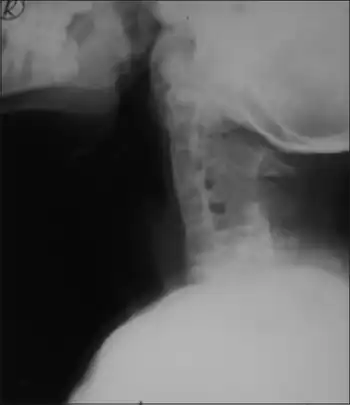

| X-ray -fused cervical vertebrae | |

- Klippel-Feil anomaly (fused cervical vertebrae)